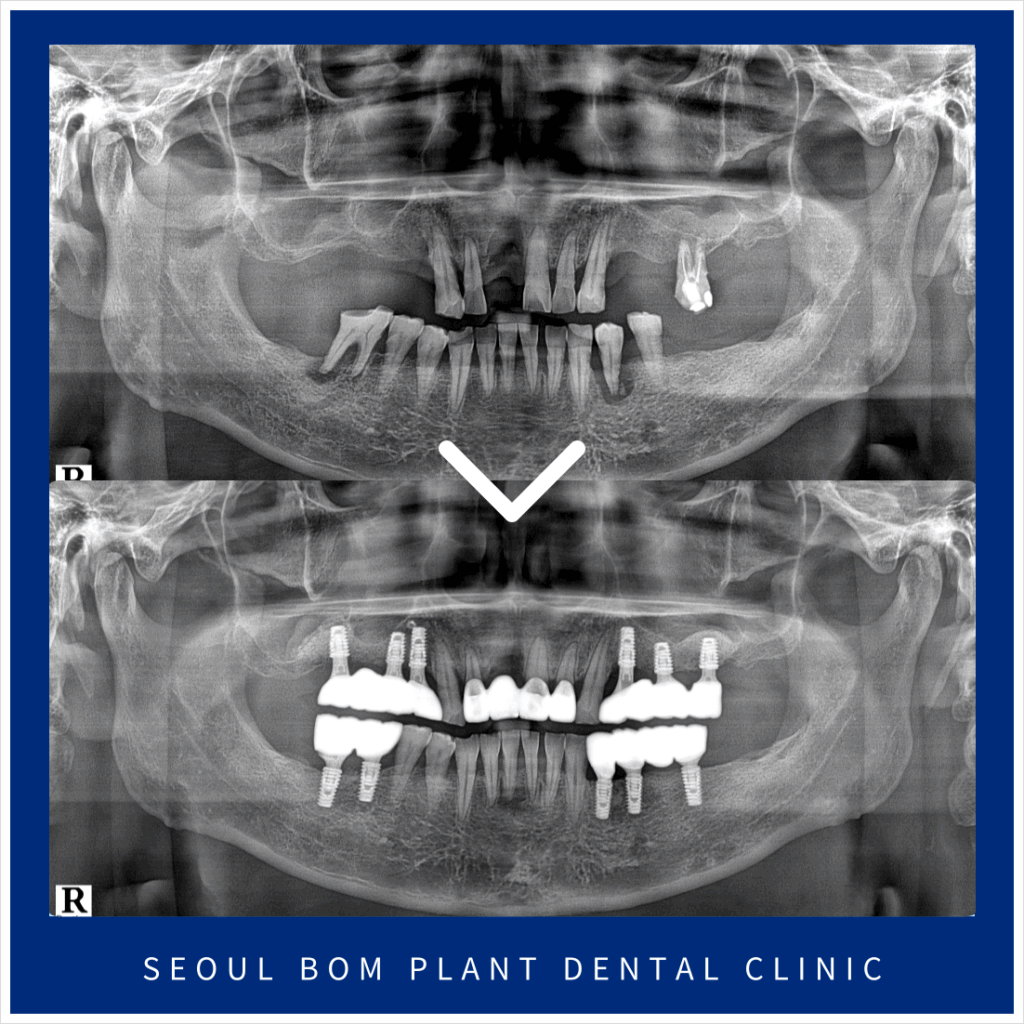

오늘은 위턱 앞니의 임플란트 탈락으로

송파구치과 서울봄플란트치과를

내원해 주신 사례를

소개해 드리겠습니다.

환자분께서는 50대 초반의

남성분으로 타 치과에서 했던

오른쪽 위턱 첫 번째 앞니(#11)의

임플란트가 빠져 상담을 위해

내원해 주셨는데요.

앞니는 원래도 잇몸뼈가 얇은 데다가

환자분께서는 임플란트 주위염으로 인해

잔존 잇몸뼈가 약해져

기존 임플란트가 탈락한 상황이었는데요.

정밀한 검사를 위해

파노라마 사진을 촬영해 보았더니

잇몸뼈 소실로 많이 약해져 있는 상태라

다시 임플란트를 식립하기에는

무리가 있었습니다.